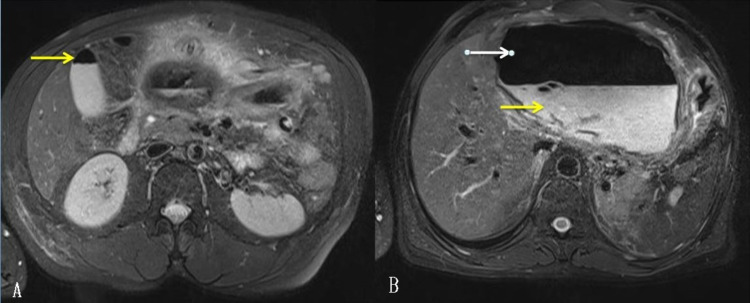

Magnetic resonance cholangiopancreatography (MRCP) showed a well-defined large cyst of 15cm x 15cm, probably arising from the left lobe of the liver with an air-fluid level in the epigastric region with pigtail inside. CBC could not be demonstrated clearly (Figure 3).

MRI is helpful in the diagnosis of HHC. It shows a hypointense pericyst on T1 weighted images, hyperintense cyst on T2 weighted images. The presence of CBC can be suggested by the presence of fat density within the cyst. It provides good visualization of the relationship of the intrahepatic and extrahepatic biliary tree with the cyst [ref. 9]. In our case, MRCP showed normal caliber CBD without any apparent communication with the cyst.